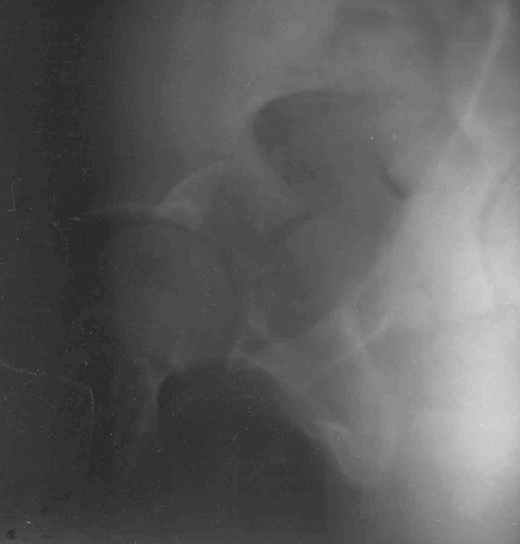

11Judet 1Judet 2

Согласно договорённости с А.В. Рунковым высылаю КТ и скиаграмму (со сканами рентгенограмм опять проблемы) 29-летнего пациента после автотравмы. С Уважением Андрей Стасюк

Там смещение есть и на уровне свода тоже...